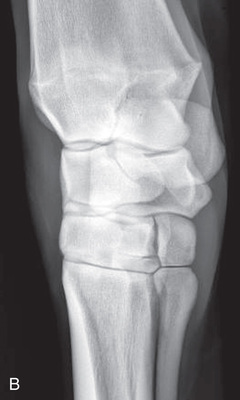

| Carpus | Dorsoproximal-palmarodistal (DPr-PaDi) | Dorsopalmar (DP) |

| Lateromedial extended (LM) | Lateral (L) | |

| Lateromedial flexed (LM) | Flexed lateral (L) | |

| Dorsoproximal 45-degree lateral–palmarodistomedial oblique (DPr45L-PaDiMO) | DLPMO | |

| Dorsoproximal 45-degree medial–palmarodistolateral oblique (DPr45M-PaDiLO) | DMPLO | |

| Optional views | Dorsoproximal-dorsodistal oblique flexed (DPr-DDiO) | Skyline |

The carpus consists of three principal joints with articulation between adjacent bones in each row of carpal bones. This causes overlying images, which may confuse interpretation. Consequently, it is recommended to obtain a minimum of five standard views.3

Oblique views of the carpus are as follows: